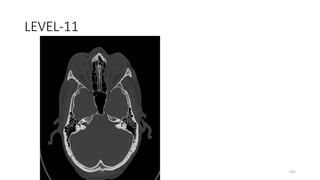

LEVEL-11

Internal auditory canal

Middle ear with malleus and incus

SQUAMOUS OCCIPITO

OCCIPITO MASTOID SUTURE

BODY SPHENOID

GREATER WING SPHENOID

Sphenosquamous suture

PETROUS TEMPORAL

SUPERIOR ORBITAL FISSURE

VESTIBULE WITH SEMICIRCULAR CANAL